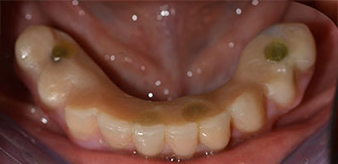

La patiente âgée de 64 ans présente une denture résiduelle des dents 38, 33 et 43 et une prothèse amovible mandibulaire stabilisée par crochets (Fig. 1 et 2).

Un CT Scan à faisceaux coniques tridimensionnel (CBCT, Planmeca) a été réalisé au préalable afin de réduire les risques. Il a révélé une qualité et une quantité d'os disponible suffisante pour l'intervention chirurgicale et la restauration immédiate par la méthode All-on-four. En suivant le protocole de ce concept, les implants sont insérés au niveau de 35, 32, 42 et 45 en inclinant les implants distaux jusqu'à 45°, le profil d'émergence se déplace ainsi vers l'arrière et produit un polygone de stabilisation plus large (Fig. 3).